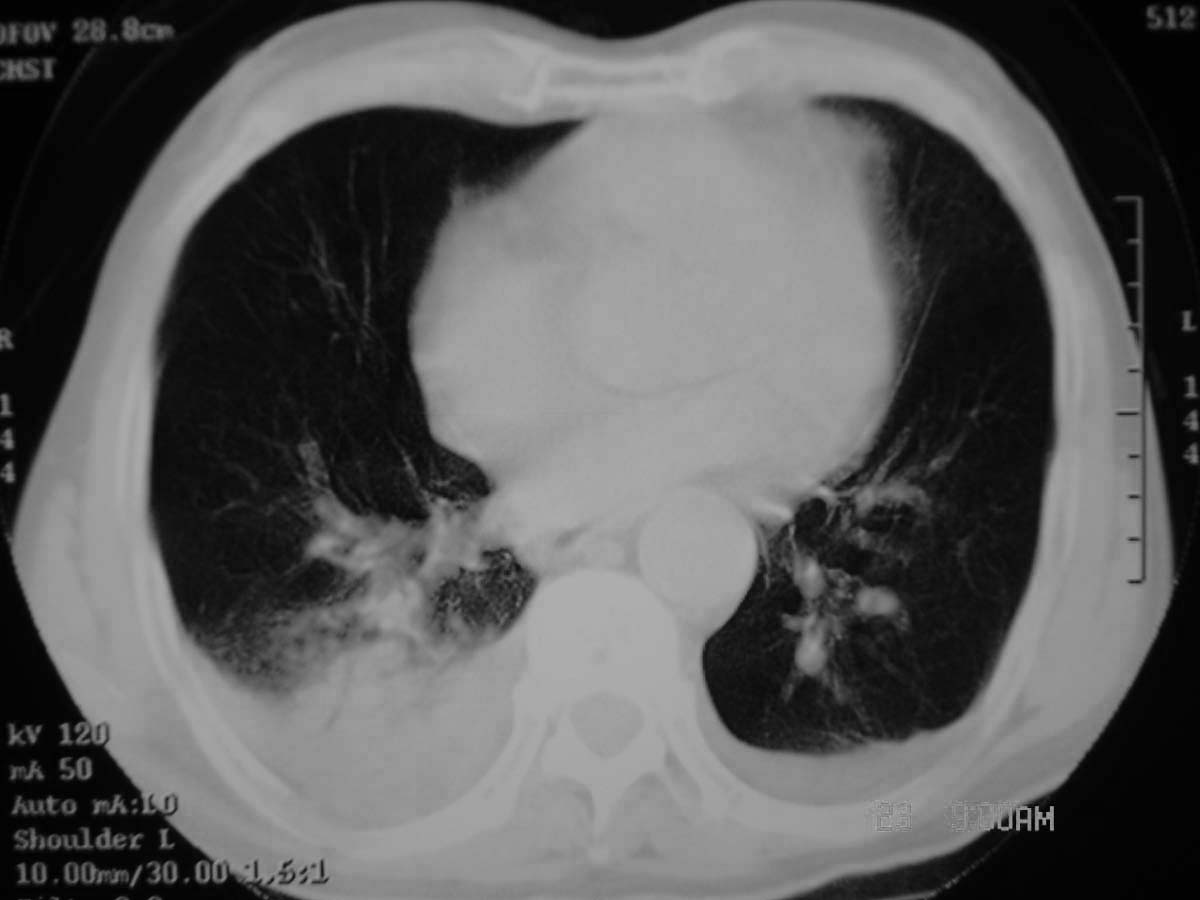

以下是引用守望可可西里在2006-11-23 14:33:00的发言:[br][br] 糖尿病病人很容易继发结核,病人又有双侧胸膜增厚、粘连、胸腔积液以及双上肺的斑片状、条索状影结核病灶影,以一元论考虑,右下肺病变首先考虑干酪性肺炎,可以正规抗炎治疗后复查,排除一般的肺炎。